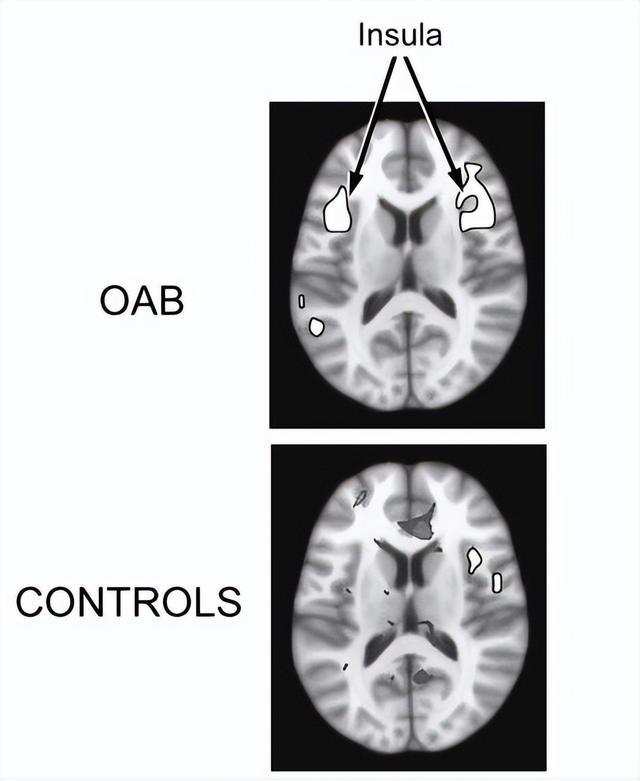

膀胱中只好少许尿液时,膀胱过度敏锐的患者(上)

与对照组(下)的大脑激活情况